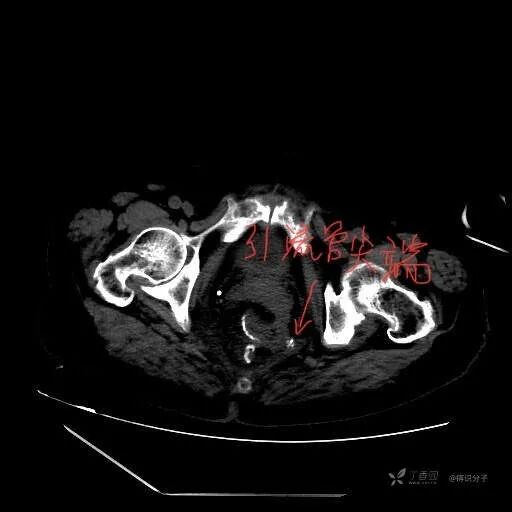

辅助检查:查腹部 CT 示骶前包裹性积液,距离引流管较远,吻合口周围未见明显渗出和气体征象。

3 天后经肛门注入碘海醇,CT 未见明显漏出征象。